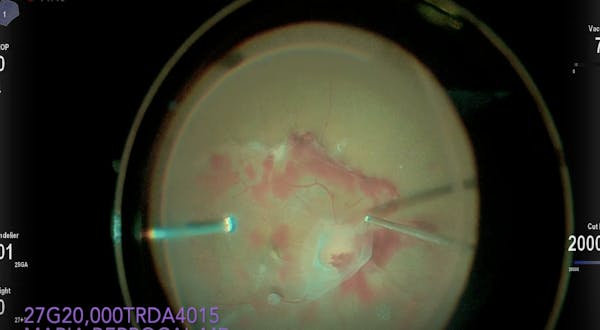

Maria H. Berrocal, MD, Timothy G. Murray, MD, MBA